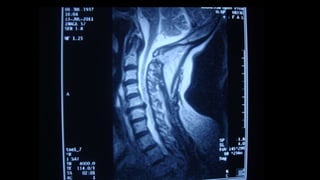

Paraparesis: dorsal spine MRI, with or without contrast or in some

cases, brain/cervical MRI (with or without contrast).

Quadriparesis: brain/high cervical cord MRI, with or